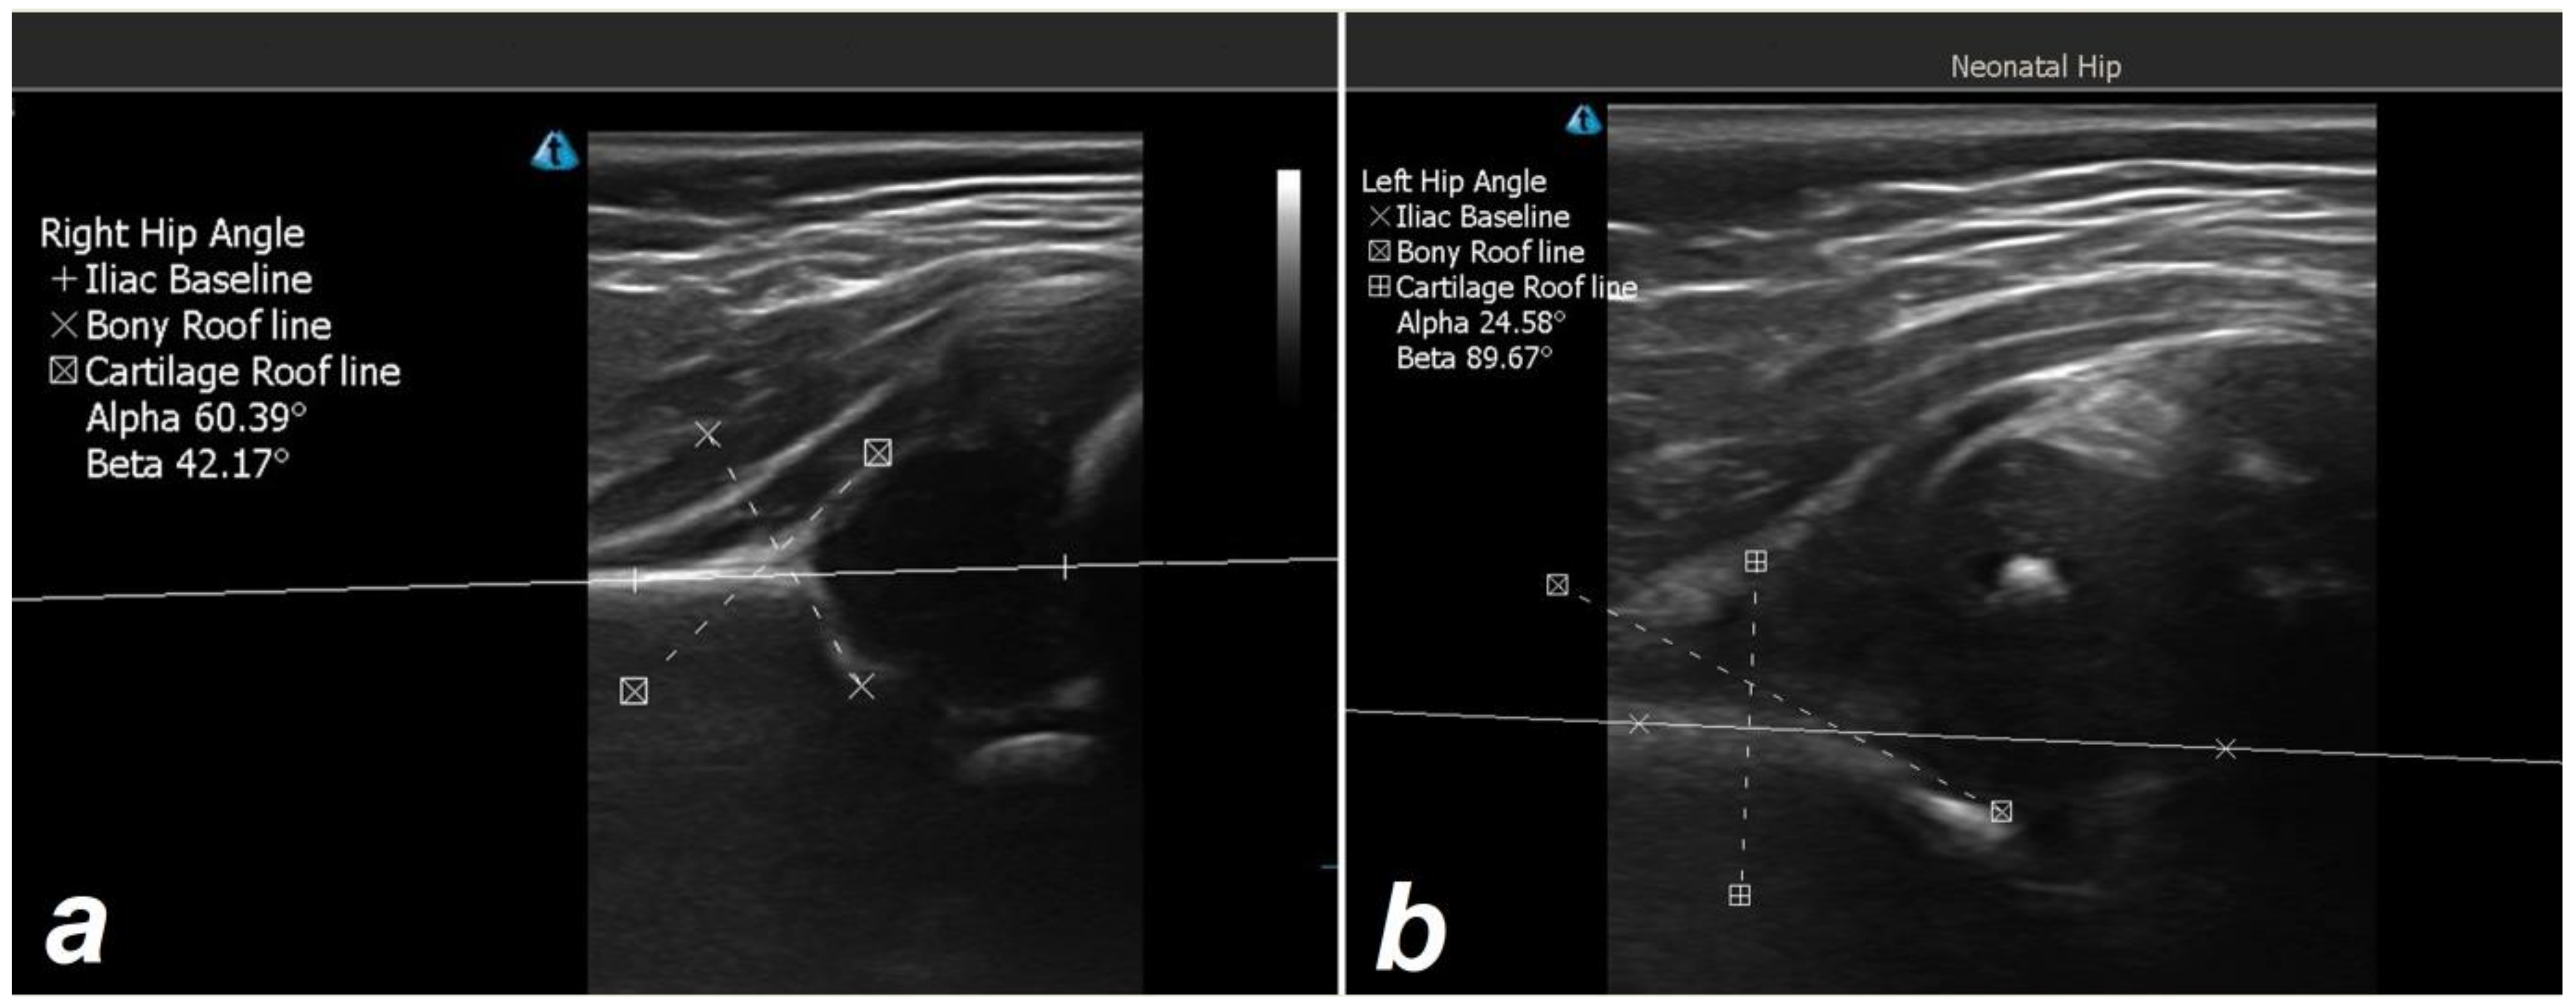

- Graf, R. Hip sonography: 20 years experience and results. Hip Int. 2007, 17, 8–14. [Google Scholar] [CrossRef]

- Õmeroğlu, H. Use of ultrasonography in developmental dysplasia of the hip. J. Child. Orthop. 2014, 8, 105–113. [Google Scholar] [CrossRef] [PubMed]

- Graf, R. Hip sonography: Background; technique and common mistakes; results; debate and politics; challenges. Hip Int. 2017, 27, 215–219. [Google Scholar] [CrossRef]